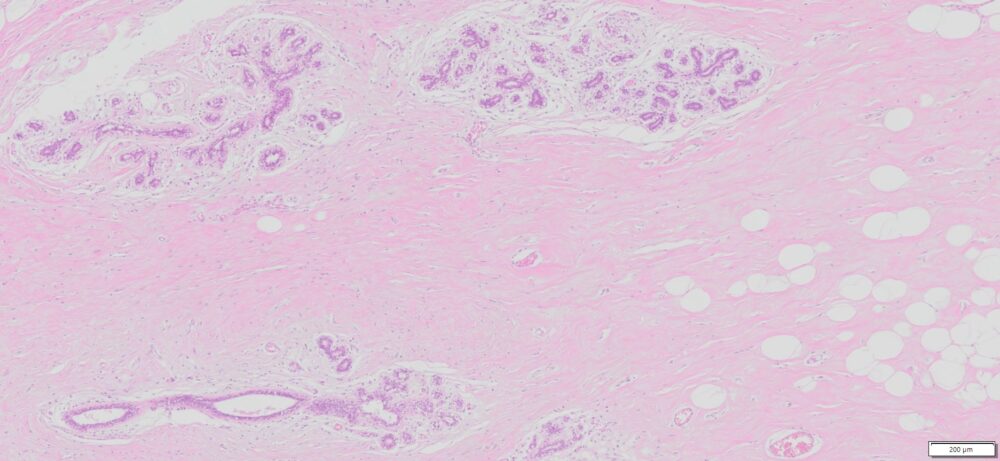

| SKU# | Organ | Pathology Diagnosis | Gender | Age | Grade | TMN | Thickness | IHC Tested |

| HuPS-02006A | Human Breast | Normal breast tissue | Female | 75 | — | — | 5um |

Human tissue was fixed in formalin immediately after excision and embedded in paraffin. The tissue sections were 5 µm in thickness and mounted each on positively charged glass slides.